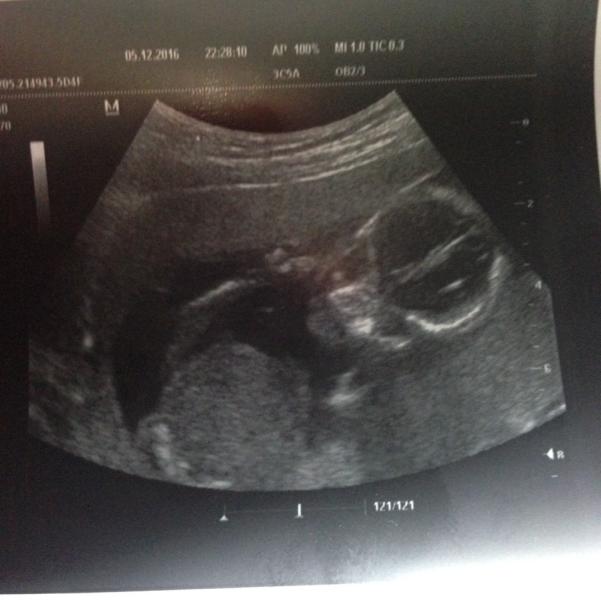

Счастье моё маленькое ☺️😍❤️ Мой сыночек 😍🌸💋